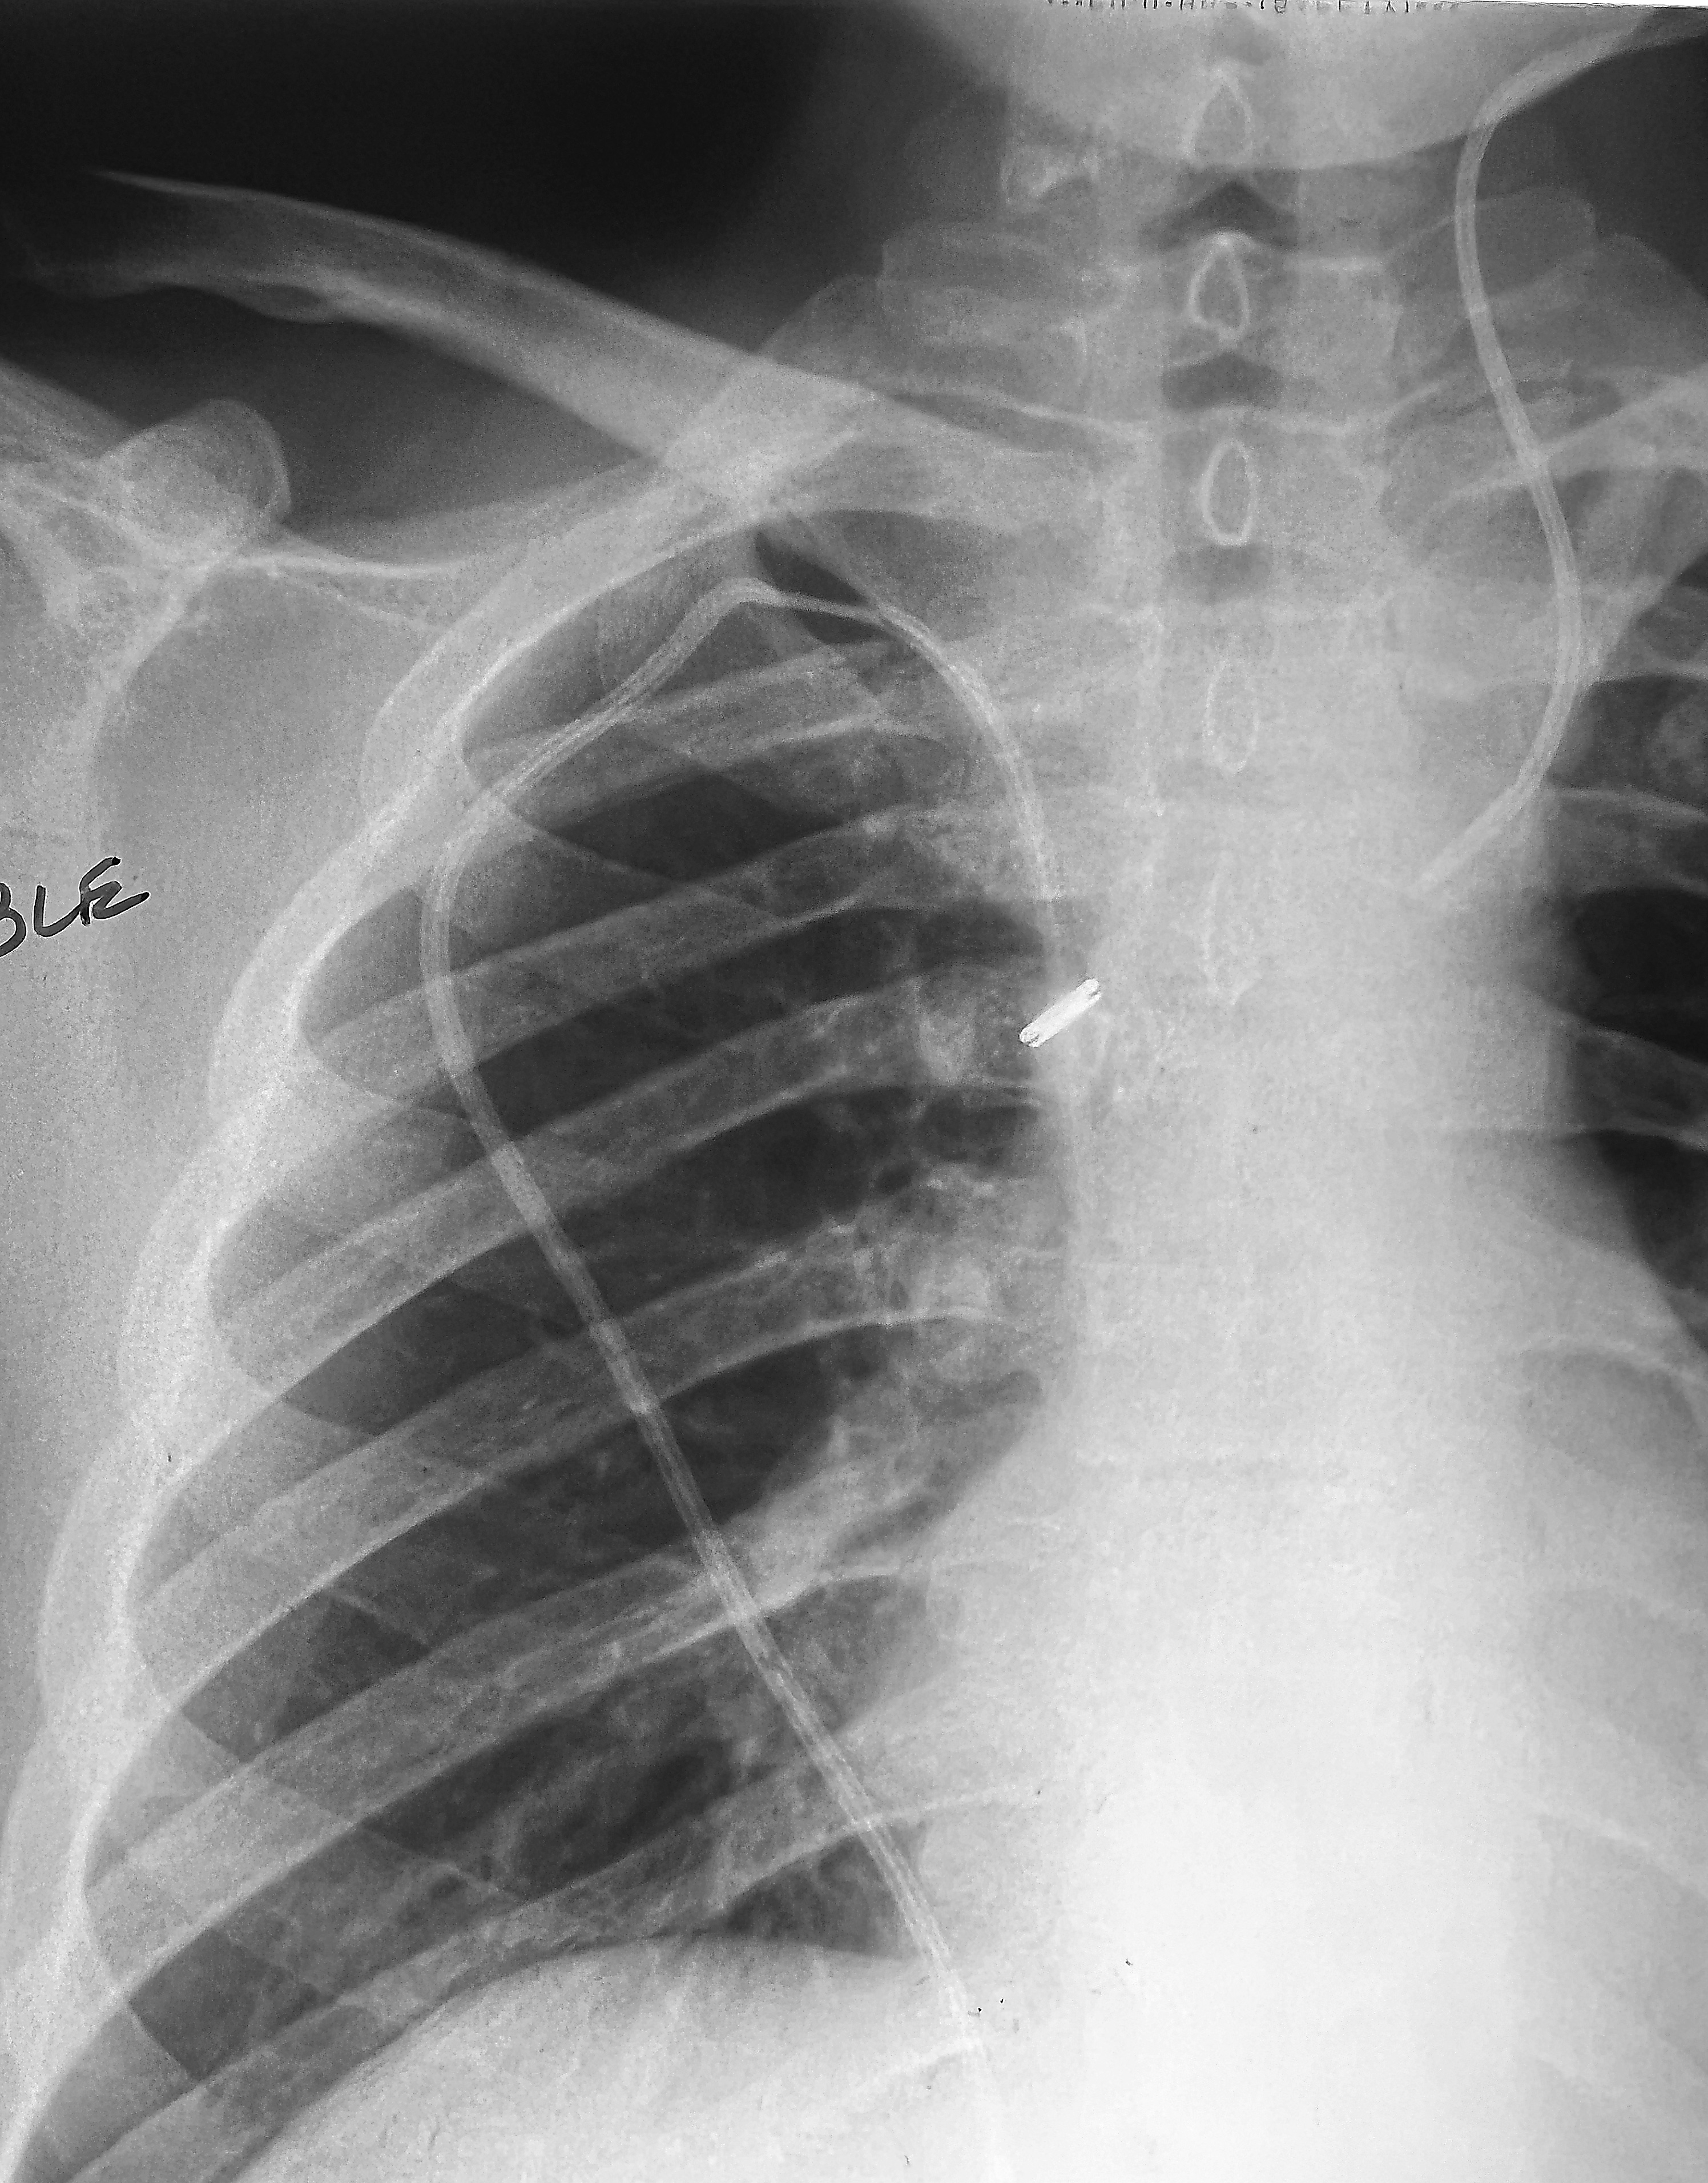

◂Breast Anatomy